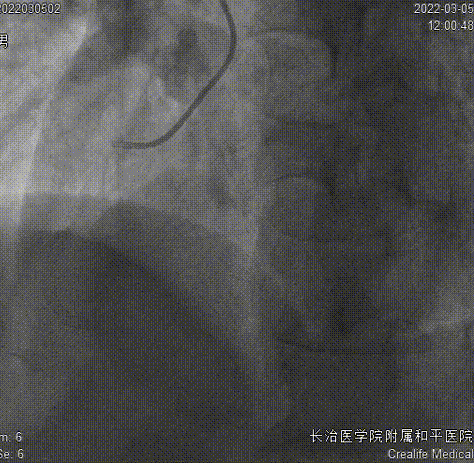

残余狭窄、肌桥

药物球囊2.75x35mm、Telescope™导引延长导管

药物球囊定位、释放

结果